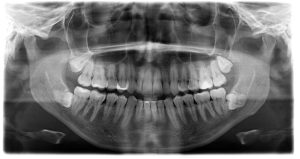

The emergence of wisdom teeth, also known as third molars, is a rite of passage for many individuals. These teeth typically make their appearance in late adolescence or early adulthood. While some people may have enough space in their mouths for these extra molars, others may encounter issues such as impaction, crowding, or pain. At Smile with Grace Dental Care, under the expert guidance of Dr. Grace, wisdom teeth removal is a routine procedure that ensures a smooth and painless experience. In this comprehensive guide, we’ll explore the world of wisdom teeth removal and highlight the compassionate care provided by Dr. Grace’s practice.

Wisdom teeth removal is a common dental procedure, often recommended for the following reasons:

Impaction: Wisdom teeth frequently do not have enough space to emerge properly, leading to impaction. Impacted teeth can become painful and cause various dental issues.

Crowding: Wisdom teeth can exert pressure on neighboring teeth, leading to crowding and misalignment.

Infection: Partially erupted wisdom teeth can create pockets where bacteria can accumulate, leading to infection and gum disease.

Pain and Discomfort: Emerging wisdom teeth can cause pain and discomfort in the mouth, jaw, and even headaches.